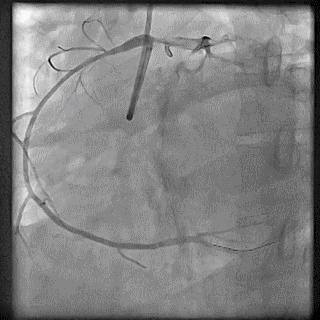

➢ CASE 1

➢ CASE 2

右冠起源异常,开口于左冠窦